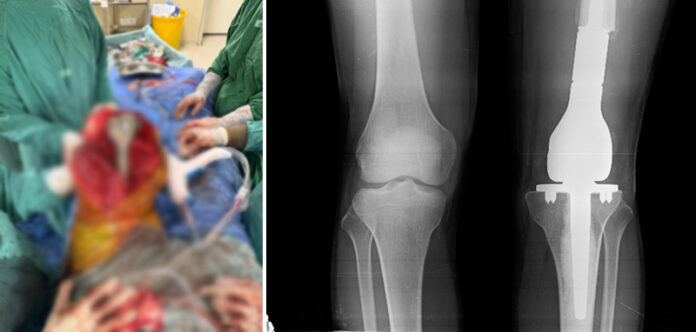

Under the supervision of Dr. Adil Hassan from Medical Oncology, the patient underwent neoadjuvant chemotherapy and showed an excellent metabolic response on PET-CT scan. This was followed by a highly specialised limb salvage surgery using a modular prosthesis, performed by Dr. Kiran Kamalasanan from Surgical Oncology. The complex procedure, available at only a few centres in the region, allowed preservation of the limb and long-term mobility. Post-surgical histopathology confirmed a complete pathological response with clear margins, and the patient successfully completed adjuvant chemotherapy.